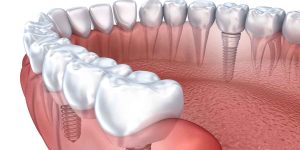

A beautiful smile can boost your confidence and enhance your overall appearance. With advancements in cosmetic dentistry, achieving your best smile is now more accessible than ever. Modern technology has revolutionized dental treatments, making them more effective, efficient, and comfortable. This article will explore the various cosmetic dentistry technologies that can transform your smile, their benefits, and how they contribute to better dental health and aesthetics. What is Cosmetic Dentistry? Cosmetic dentistry focuses on improving the appearance of your teeth, gums, and overall smile. It encompasses a range of procedures designed to address aesthetic concerns such as discoloration, misalignment, gaps, and damaged teeth. While the primary goal is to enhance the visual appeal of your smile, many cosmetic treatments also